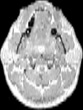

Visible Human male: Sectio transversalis 1188

CT

NMR

Pd T1 T2